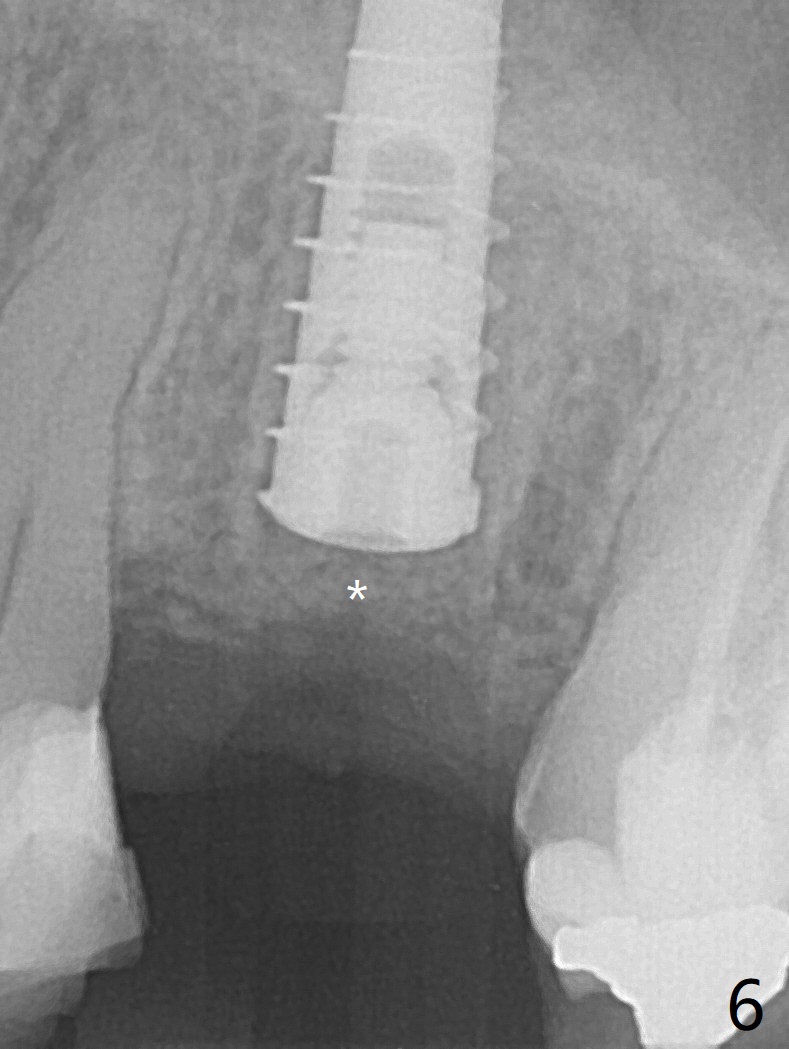

The patient with the anterior cross bite at the left lateral and canine and incipient Class V caries returns to clinic for #13 residual root extraction (Fig.1,2). There is no quality root structure (Fig.2) or space (Fig.3) for socket sheath. Two amalgam carriers of Vanilla is inserted and pushed by the 4x11 mm dummy implant for sinus lift (Fig.4 *). When the same sized final implant (4x11 mm) is placed, a 5.5 mm bone profile drill is used to trim the proximal crests (Fig.5 * sticky bone packed in the buccal and palatal gaps). In fact the implant turns when a 4.5x4(3) mm pair abutment is tightened. The implant is backed up; with a healing screw, sticky bone is placed (Fig.6 *) and then covered with a piece of PRF and a part of GEM cap. The wound is sutured with 4-0 PGA; periodontal dressing is applied. The implant is somewhat over-seated without the bone graft covering the apical end of the implant (Fig.7, as compared to Fig.4). A 4.5 mm implant should be placed. The GEM Cap appears to be absent 9 days postop, while the periodontal dressing dislodged in 1 week (Fig.8). It appears that the existing abutment at #15 is incompletely seated (Fig.3, 5.5x4(2) mm). After use of 5.5 and 6.0 mm bone profile drills, a 5x4(3) mm abutment is placed with 35 Ncm torque. In fact the bone graft coronal to the implant remains (Fig.9 *) in spite of apparent loss of the overlying PRF and GEM cap (Fig.8). After use of a 4.6 mm profile drill, a 5.5x3 mm healing abutment is placed 4.5 months postop (Fig.10). Without a provisional at #13 for ~ 4 months, there is a gap between crowns at #14 and 15 (not shown due to angulation). Impression is taken for #13 crown fabrication 5.5 months postop and for #15 crown repair (addition of porcelain for the mesial contact, Fig.11). It appears critical for a provisional to maintain the position of the neighboring tooth.